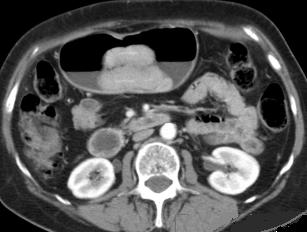

Lymphome gastrique :

Une epaississement diffuse a hypodense mais sans

stenose de l' estoma ( image TDM en coupe axiale ) .N'a

pas de rigidite a la region lesionaire |